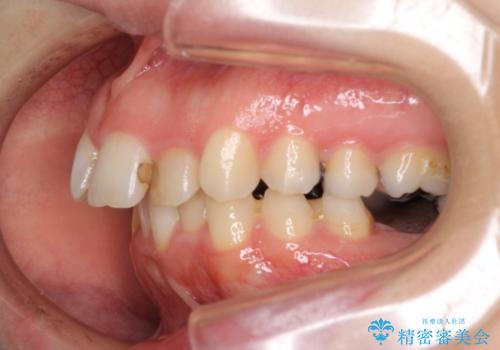

目立たないハーフリンガル矯正を希望され、裏側装置はどうしても清掃性が低下し、むし歯発生のリスクが高まるため、矯正治療前にしっかりとむし歯治療を行い、矯正治療後にセラミックによる補綴治療を行うこととしました。

抜歯したスペースがなかなか閉じず、治療に時間はかかりましたが、術前術後のむし歯治療と合わせて3年10ヶ月で治療を終えることができました。

途中結婚により遠方に引っ越しをされたため、むし歯治療は取り急ぎ目立つところをセラミッククラウンとしましたが、今後落ち着いてきたら他の部分も行っていく予定です。